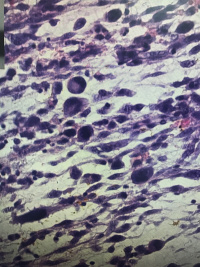

左小腿包块

性别

男

年龄

39

渐增性包块四月,伴破溃流血一月

灰白组织一堆,大小10✖️6✖️4.5,切面灰白灰红,黏液感,

粘液性纤维肉瘤